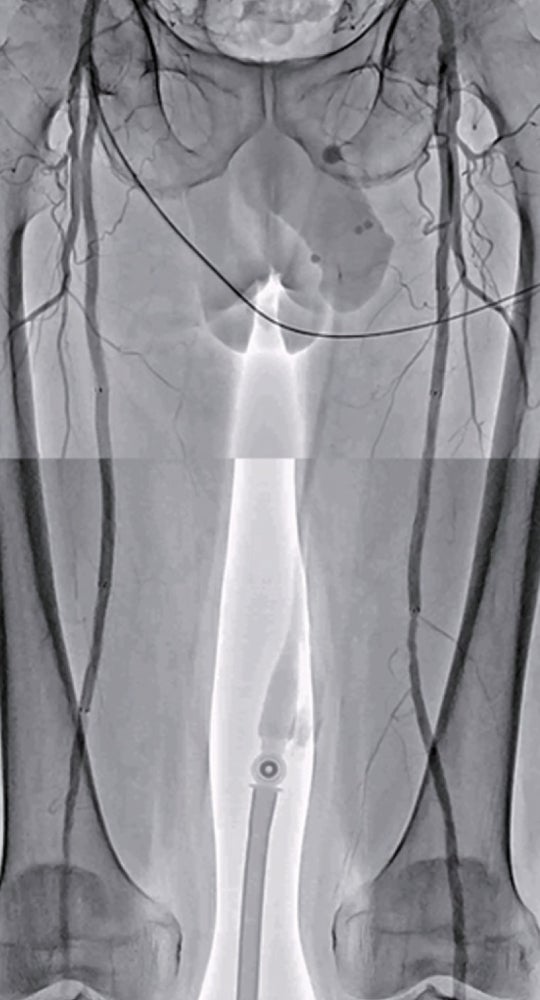

右浅大腿動脈閉塞(図3): 左鼠径部を穿刺(6 Fr シース)しcrossover後、順行性に0.014 inchマイクロカテーテルを使用して0.014 inch ガイドワイヤー(先端荷重1 g →3 g →40 g)を進めたが貫通できず、足背動脈を穿刺し逆行性に0.014 inch ガイドワイヤーを進め、貫通に成功。IVUS catheterで一部 subintimal trackingしていることを確認。5.0 mm 径バルーン(non-compliant balloon)で拡張後解離が生じ、末梢にバイアバーン® ステントグラフト5.0 × 150 mm、中枢に6.0 × 250 mm の2本を留置。病変の末梢には発達した2本の側副血行路を伴い、側副血行路の間に軽度狭窄病変を認めたため、中枢側の側副血行路をjailさせ、健常部にバイアバーン® ステントグラフトを留置。5.0 mm 径と6.0 mm 径バルーン(non-compliant balloon)で後拡張して終了。(図4)

バイアバーン® ステントグラフト留置後3年経過した現時点において跛行症状の再発やTLR なく、ABI 値は正常値 ( 右1.05 左1.05) を維持し、良好。

両側浅大腿動脈閉塞病変に対してバイアバーン® ステントグラフトにて血行再建術を施行し、その後3年の経過において良好な経過をみている(図5)。側副血行路を温存するかどうかの議論はあるが、バイアバーン®ステントグラフトを健常部に留置し、遠位部に残存狭窄を残さないことが重要と考えている。さらに定期的な duplexでのフォローアップで、ステントedgeや中枢側の新規病変を早期発見し治療することが、ステント閉塞予防に不可欠と思い、実践している。最後に、長区域の浅大腿動脈病変の治療は、外科治療のオプションも見据え、血管外科医との連携は極めて重要と考えている。